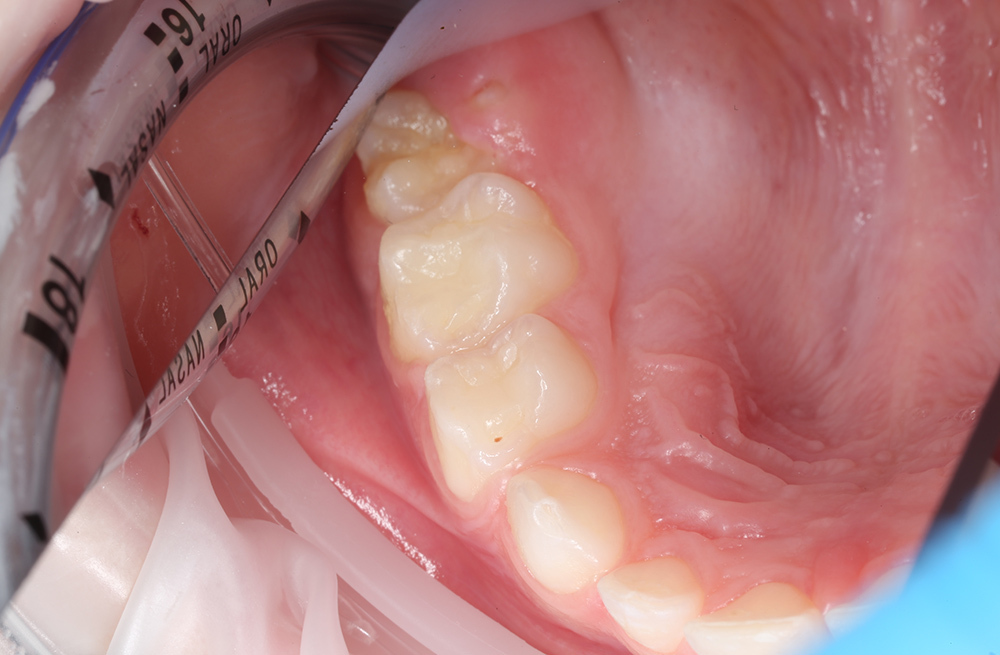

Герметизация фиссур первого постоянного моляра у шестилетней девочки с неудовлетворительной гигиеной